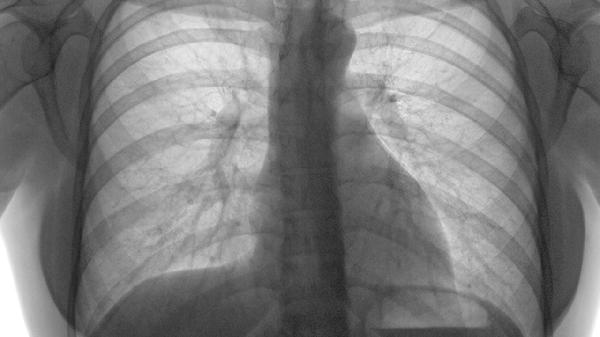

单侧小腿肿胀伴压痛可能提示深静脉血栓,突发呼吸困难合并胸痛需警惕肺栓塞。恶性肿瘤、近期手术史等高风险人群出现不明原因心率增快时,应及时进行D-二聚体检测和血管超声检查。孕妇及口服避孕药女性出现下肢不适时应优先排除血栓。